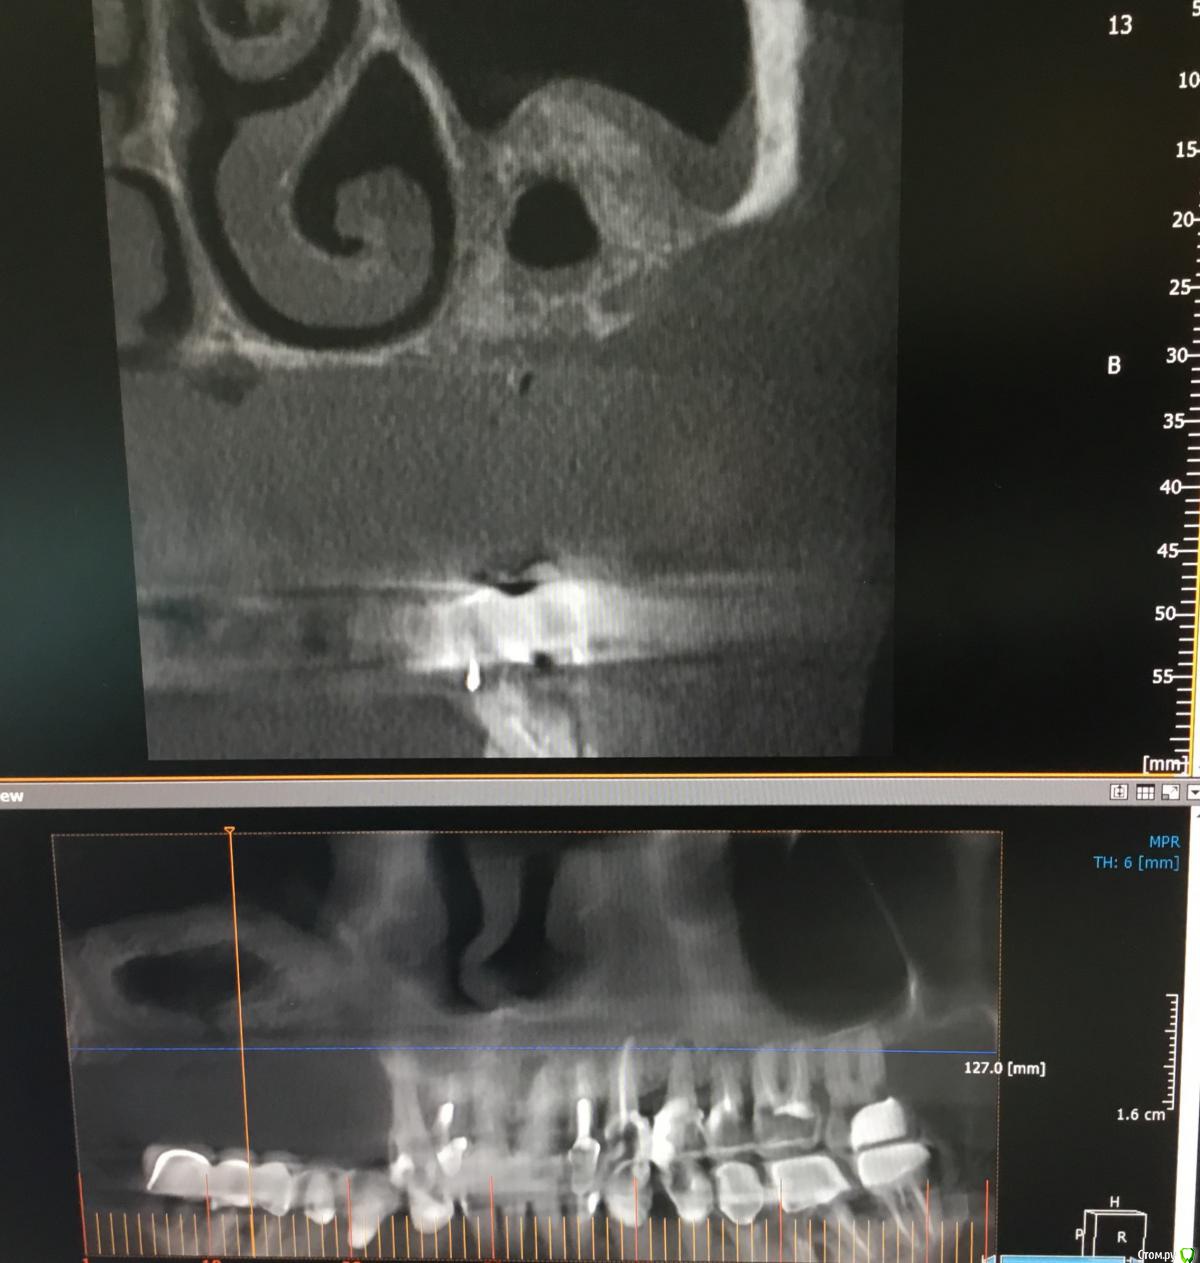

Zorrro Опубликовано 17 января, 2017 Поделиться Опубликовано 17 января, 2017 (изменено) У меня была похожая в чём-то ситуация,когда создалось впечатление мнимого благополучия.Сейчас скину скан кт. Что меня больше всего сбило с толку,так это абсолютно ровный наружный контур аугментатаи не воспалённая мембрана синуса… Изменено 17 января, 2017 пользователем Zorrro 4 Ссылка на комментарий

Zorrro Опубликовано 17 января, 2017 Поделиться Опубликовано 17 января, 2017 Чем закончилось?Повторным синусом,если можно это так назвать.Изначально у пациентки была очень тонкая костная стенка ,местами не заросшая после удалениятак что после неудачного первого синуса получил довольно большой дефект.Ситуация доЧерез 6 месПосле удаления каши из синуса,решил подстраховаться и выстелил дно мембраной,припинив её к небной стенке изнутри и к латеральной стенке снаружи.Потом титановая сетка,которую перекрыл коллагеновой мембранойПерекрестил и ушил.ждём … 1 Ссылка на комментарий